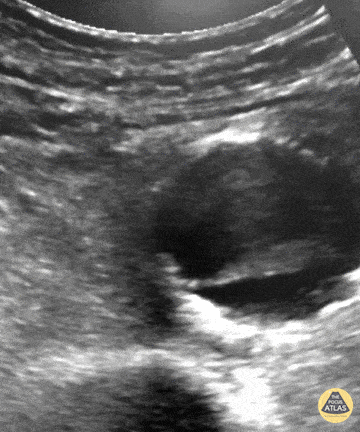

Aorta - Pulsating Aortic Aneurysm

You may think this a dissection but it's actually an aortic aneurysm filled with thrombus, "with holes" making it a very "happy flappy." CT Confirmed. Dr. Vincent Rietveld - Amsterdam, The Netherlands